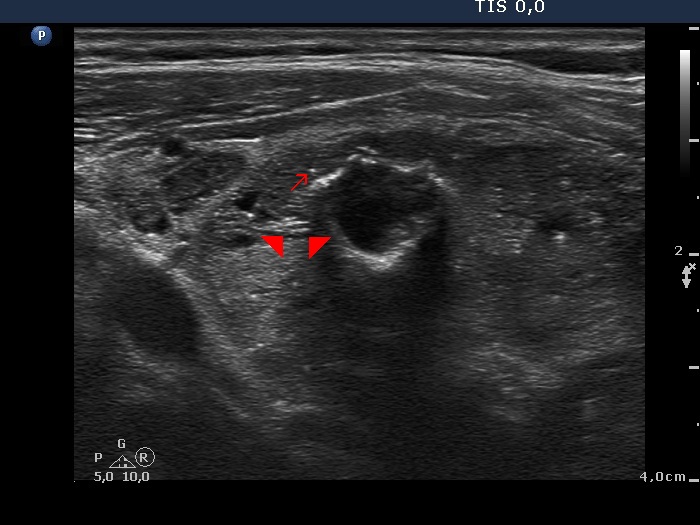

Follicular adenoma (histological diagnosis) - case 1519 |

|

The acoustic shadow points to coarse calcifications. On the other hand, the ventral thick hyperechogenic curves only partly correspond to coarse calcification because of the lack of acoustic shadow alongside the figure.